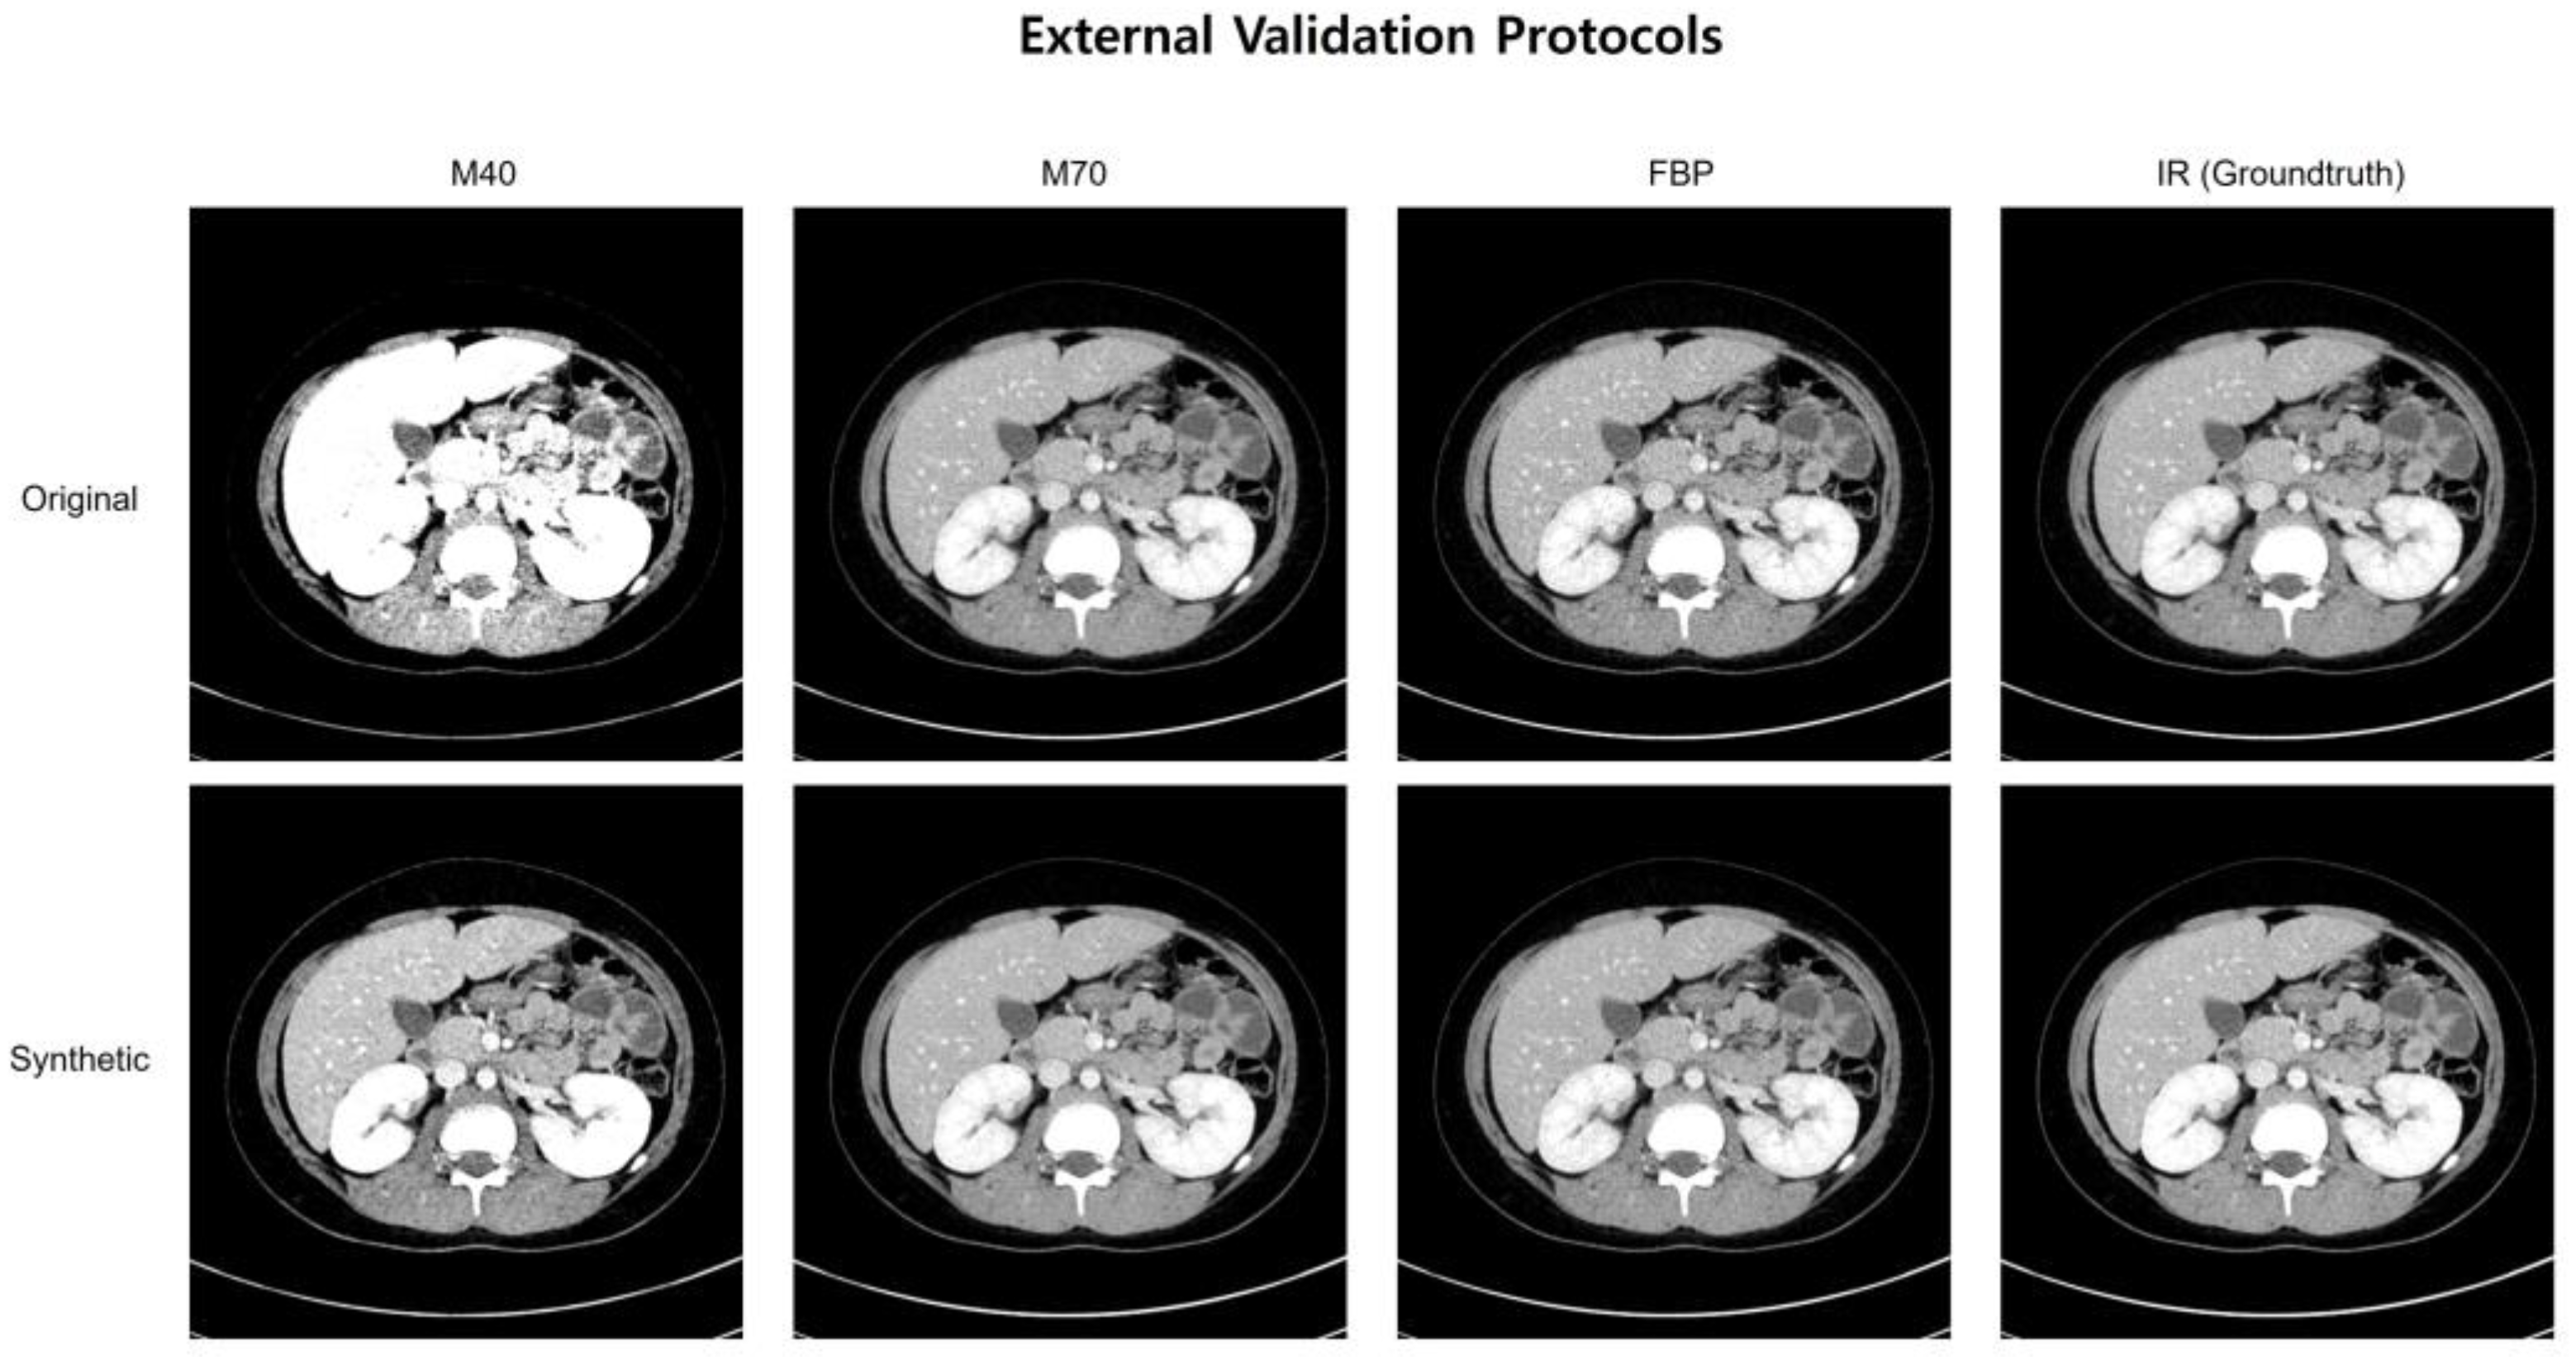

3.2. Patient-Based Reproducibility Analysis

| Reconstruction methods | FBP, IR, M40, M60, M80, OPT † | FBP, IR, M40, M70 † |

| External Validation | ||||||

| Original | 75 (19%) | 68 (18%) | 55 (14%) | 59 (15%) | 92 (24%) | 369 (95%) |

| Synthetic | 199 (51%) | 239 (62%) | 266 (69%) | 244 (63%) | 212 (55%) | 365 (94%) |

| Increase (%) | 32% | 44% | 55% | 48% | 31% | −1% |